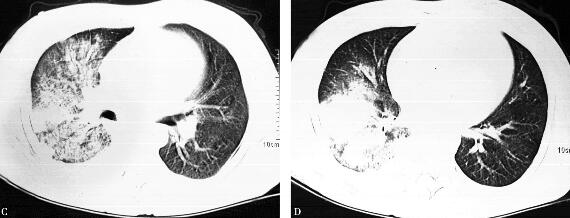

治疗10天后,咳嗽、咳痰症状逐渐消失,肺部听诊未闻及湿啰音,体温正常,消化系统、神经系统症状消失,胸部CT较前略有吸收(图3)。治疗两个月后,随访:无不适症状,胸部CT病变明显吸收(图4)。

图3